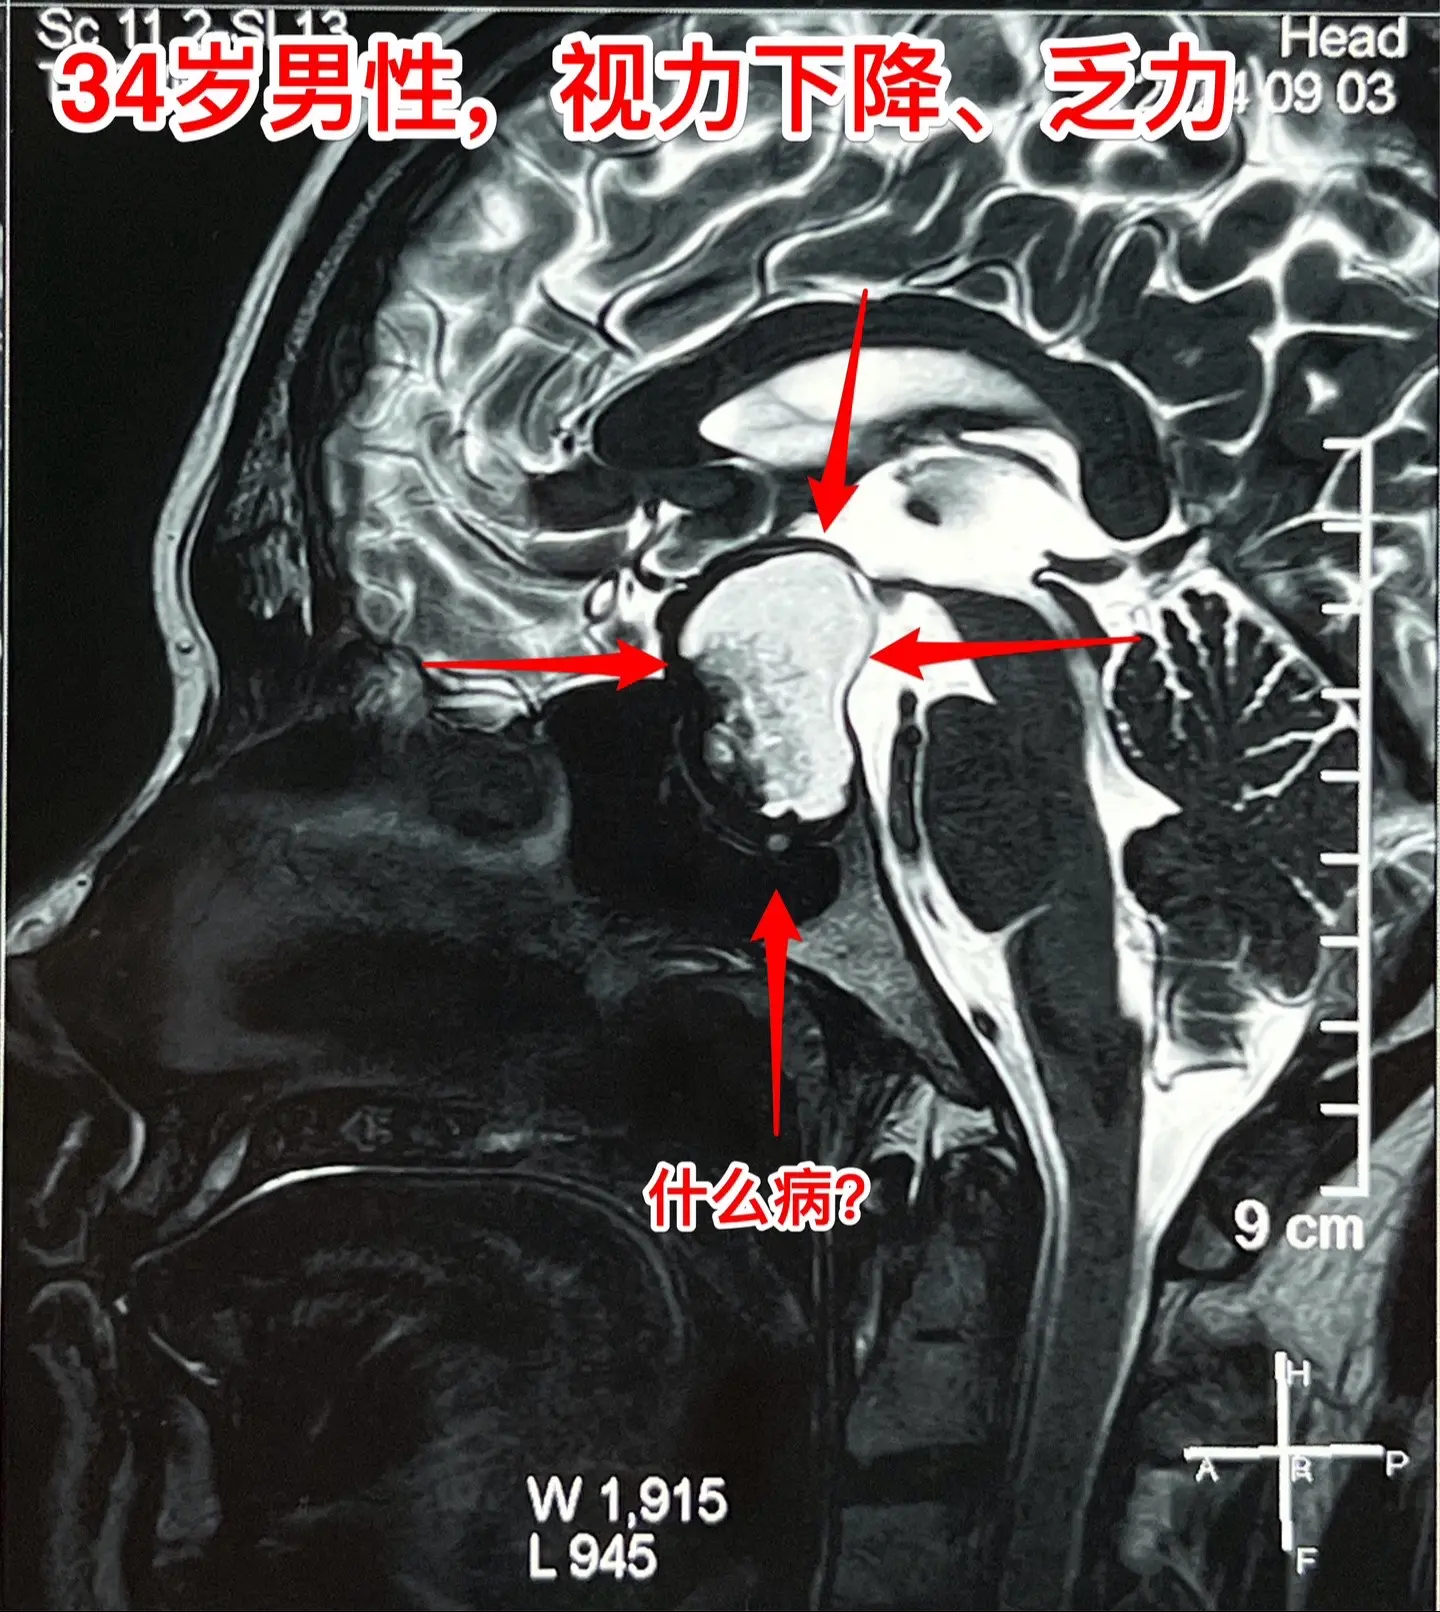

34岁男性视力下降、三个月体重下降30斤。34岁山东滕州男性,视力下降半年,头痛、恶心、乏力4个月,同时食欲不振,三个月体重下降30斤。在当地医院内分泌科住院检查,发现鞍区囊性病变,没有钙化。

这是颅咽管瘤还是拉克氏囊肿?

我们把拉克氏囊肿放在第一位。有时候这两种病还是很难鉴别的。

2024.9.2到我科住院,9月6日行开颅手术,将鞍区囊肿切除,术中见囊肿壁较薄,无钙化,囊肿得到完全切除,一部分垂体和垂体柄得以保留。